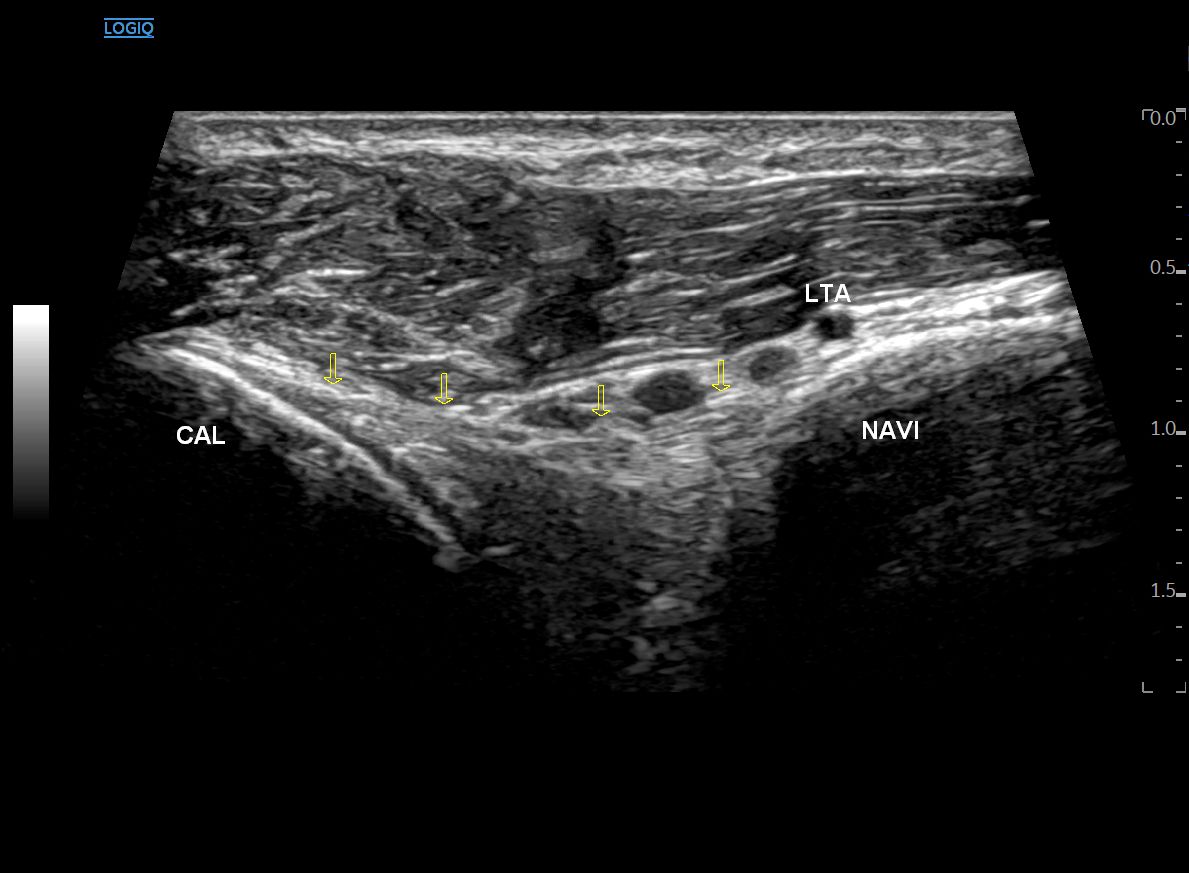

좌측 모식도 @ DOI: 10.1002/sono.12300 / 우측 초음파 영상은 직접 스캔했습니다

민트색 박스로 표시한 부위에

프로브를 댄 영상입니다.

단모지신근(EHB) 아래로

종골(CAL)과 주상골(NAVI)을 연결하는 이분인대,

즉 종주인대 섬유가 보입니다.

종주인대(CNL) 위로는

바깥 발목 동맥(LTA, Lateral tarsal artery)이 지나갑니다.